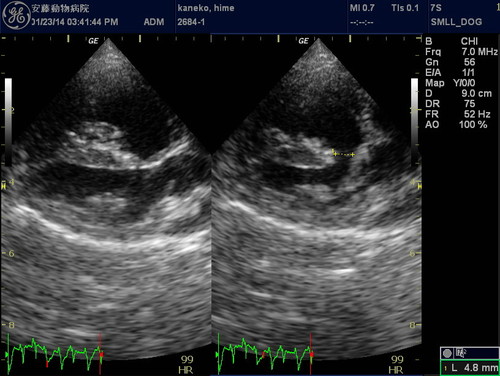

一般身体検査(聴診など)、血液検査、心電図検査、レントゲン検査、心臓エコー検査

エコー心臓・血管造影検査

心臓エコー検査・マイクロバブル造影法